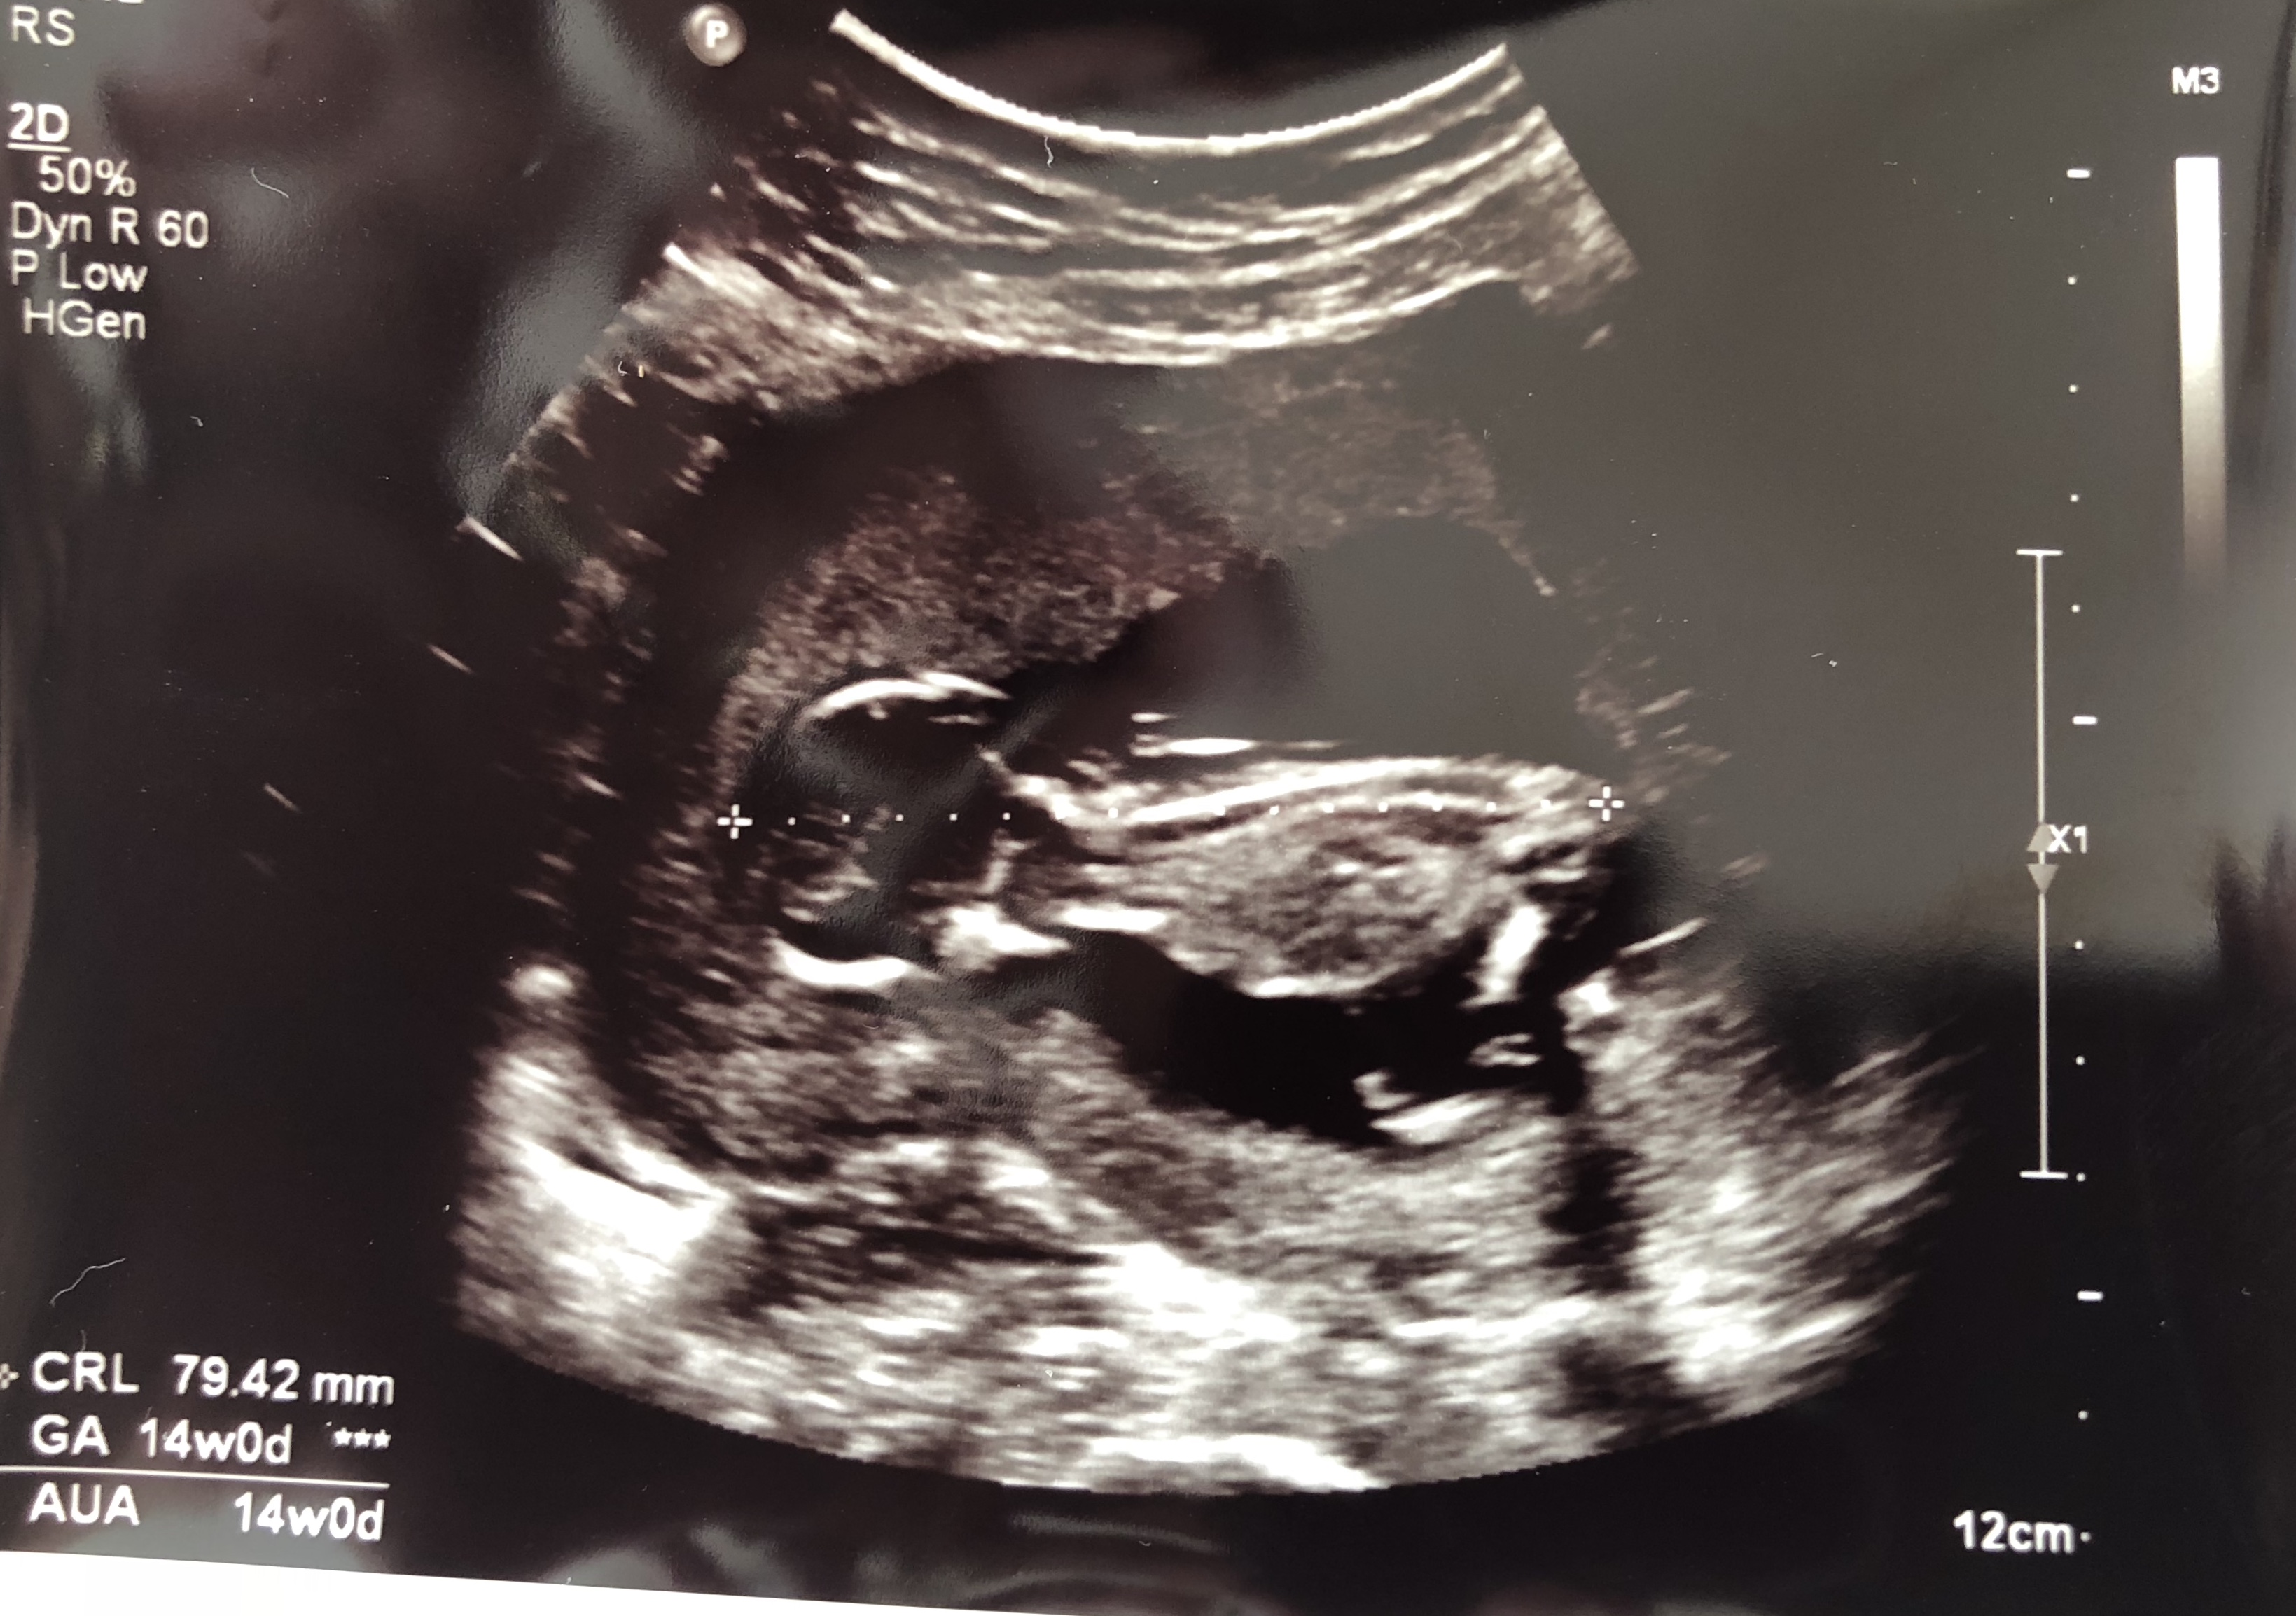

Can anyone guess my baby gender by skull theory?

Do you see nub in the 1st pic?

14w

Attachment 40780